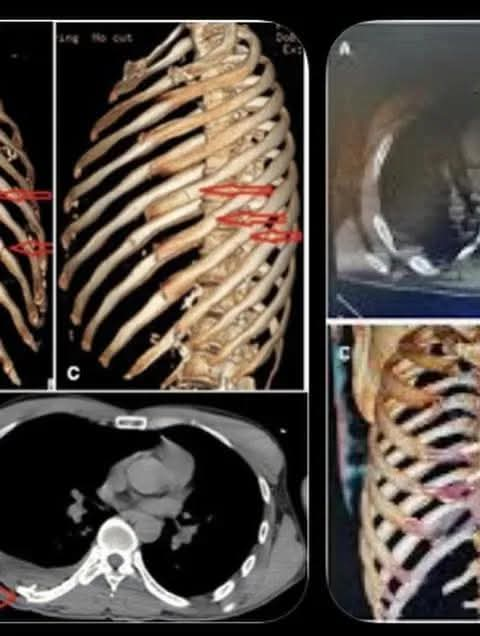

El también hijo de Rick Harrison resultó con 11 costillas rotas 🩻, un pulmón perforado 🫁, conmoción cerebral 🤕 y hemorragia interna, tras el percance ocurrido en febrero.

🚑 Finalmente fue trasladado por carretera a Mérida, donde especialistas detectaron que una costilla se había separado y presionaba el pulmón, además de una importante acumulación de sangre en el tórax.

🏥 En ese hospital le extrajeron casi tres litros de sangre de la cavidad torácica y fue sometido a tres cirugías, permaneciendo 18 días hospitalizado antes de iniciar su proceso de recuperación.